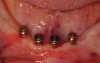

Examination of the residual ridge at the treatment-planning phase can assist in identification of any anatomic obstacles that will require use of a bar (or recommendation of a fixed approach) or when freestanding implants with attachments can be used. An anatomic landmark to keep in mind when evaluating the patient is the genial tubercles. As ridge height is lost in the anterior, the ridge crest migrates toward the genial tubercles, which results in a shallower floor of the mouth and more lifting of the prosthesis from the muscles located in this area of the mouth (Figure 9). When it is noted that the genial tubercles are positioned at or superior to the crest of the ridge, this signifies severe bone resorption. Utilization of freestanding implants is precluded, as the ridge offers no lateral bracing, and thus stability of the prosthesis is compromised (Figure 10). The same test that was recommended in the maxillary arch to test lateral stability of the current denture can be performed in the mandibular arch. This also helps illustrate to the patient why freestanding attachments are not ideally suited for the situation and why a bar would be recommended. Discovering these issues during the treatment-planning phase is better than later when the prosthetics is being fabricated and inserted.

Mini implants serve a purpose and are ideally suited with regard to removable prosthetics when the patient’s complaint is “lift-off” of the denture. Implants with “O” ring (ball) heads and attachments can provide sufficient retention to prevent the denture from lifting off the ridge during function when the patient is speaking, chewing, and using generalized tongue movements. When the patient presents with a non-implant–retained denture and the denture has significant lateral displacement, the mini implants will be loaded laterally under function. As discussed, implants manage lateral loading the worst, which leads to bone loss, mobility, or a combination of these two occurrences. The narrower the implant diameter, the less bone-to-implant contact is present (less surface area), and the less lateral loading the implant can tolerate under normal function before issues arise. Considerations for use of mini implants relates to the available ridge to provide lateral bracing as well as distribution of the implants around the arch. Due to less bone-to-implant contact, it has been recommended that when using mini implants, a minimum of 4 be placed around the arch, which is typically adequate in the mandibular arch (Figure 13). Due to lower bone quality (density) in the maxillary arch, placement of more than 4 mini implants may be a wise routine recommendation. In addition, the implants should be spaced with sufficient distance between the fixtures to distribute the retention over as much area as is available. Placing mini implants close together does not necessarily increase retention, and it thins the acrylic in the denture between the mini implant attachments within the denture, which can lead to stress fractures of the denture base.

Fig 10. Mandibular arch with negative ridge resulting from no resorption of the ridge to eliminate the vestibular depth and elevate the floor of the mouth to superior to the genial tubercles.

Figure 10

Fig 13. Mini implants with attachments in the mandible with minimal vestibular depth but adequate depth of the floor of the mouth.

Figure 13